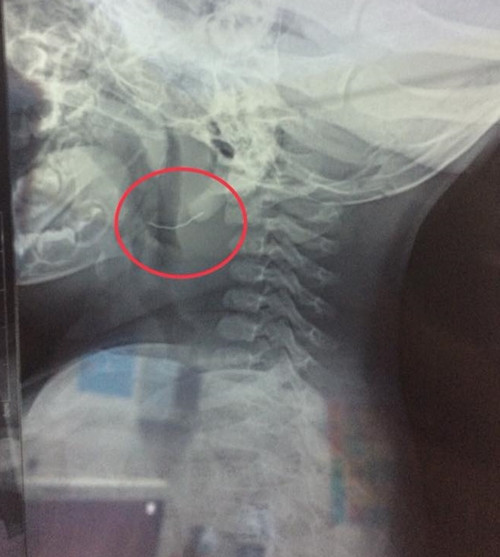

| Sợi kim loại cắm sâu 1/3 chiều dài trong họng cháu bé. |

Ngày 28/8, khoa Tai - Mũi - Họng Bệnh viện Sản Nhi Nghệ An tiếp nhập bệnh nhi 11 tháng tuổi có biểu hiện hóc dị vật. Bé đang ăn thì bỏ ăn, quấy khóc, nôn ra cháo lẫn một ít máu tươi. Sau khi kiểm tra, các bác sĩ phát hiện và tiến hành gắp bỏ sợi kim loại mảnh, nhọn hai đầu, dài khoảng 2 cm đang cắm trong vùng họng cháu bé. Nguyên nhân được xác định do sợi kim loại rớt ra từ chiếc rây lẫn trong cháo, khiến bé nuốt phải.

Bác sĩ Bùi Viết Tuấn, công tác tại khoa khoa Tai - Mũi - Họng bệnh viện Sản Nhi Nghệ An, cho hay: buổi sáng trước khi nhập viện, cháu bé được mẹ cho ăn cháo lươn và không lâu sau có những triệu chứng như trên. Nghi ngờ bé bị hóc xương, gia đình đưa cháu tới bệnh viện và kịp thời xử lý. Theo bác sĩ Tuấn, trường hợp của bệnh nhi này khá may mắn bởi dị vật chưa xuống quá sâu, lúc tiến hành gắp, sợi kim loại cắm ngập 1/3 chiều dài; hiện sức khỏe của em bé đã ổn định.